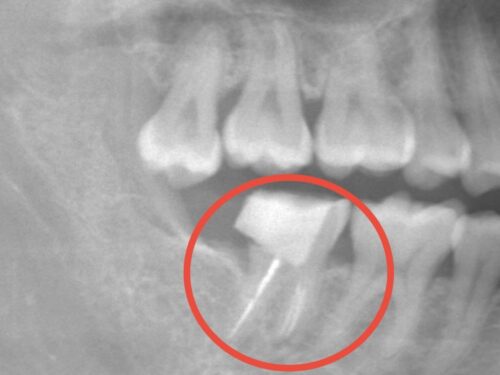

レントゲン写真を見ると、以前根管治療を受けて失活歯(神経が死んでいる歯)となっていたことがわかりました。

赤い円で示しているところです。この歯が破折してしまいました。

レントゲン検査を行い、破折の程度と周囲の骨の状態を確認しました。また、移植に使用できる親知らずについて評価しました。

赤い円で囲まれた部分に上顎の親知らずが存在していることが確認できます。

レントゲン写真で示されている上顎の親知らずを抜歯し、移植しました。